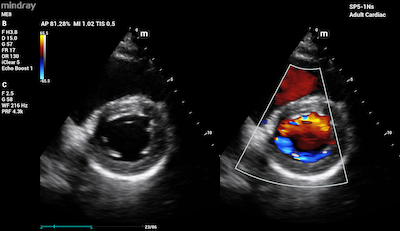

- Heart – Echocardiography utilizes a type of CDI that examines the heart and the velocity of blood flow through the cardiac valves and detects any irregularities between the left and right sides of the heart. CDI of the heart can also determine if there is any blood leakage through the valves.

Color Doppler Imaging of Mitral Valve Dehiscence